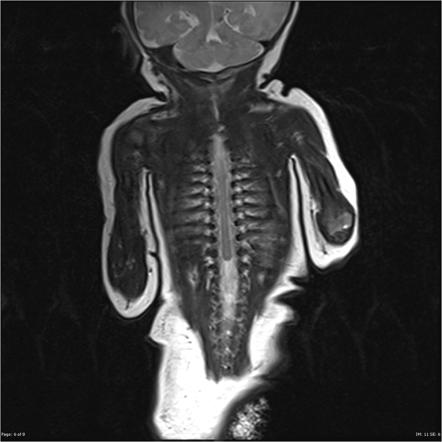

Symptoms of caudal regression syndrome vary; an affected person may not have them all. Lower vertebrae bones may not be found or ill-developed; the corresponding parts of the spinal cord are either irregular or missing as well. Incomplete closure of vertebrae may occur with the appearance of a fluid-filled sac at the back. This sac may contain only fluids or fluids with part of the spinal cord.

Diagnosis of caudal regression syndrome can be done using ultrasound during pregnancy. Doctors may be able to notice the symptoms of the disorder affecting the lower part of the body and use x-rays after birth to ensure the case and examine bones and organs’ health.